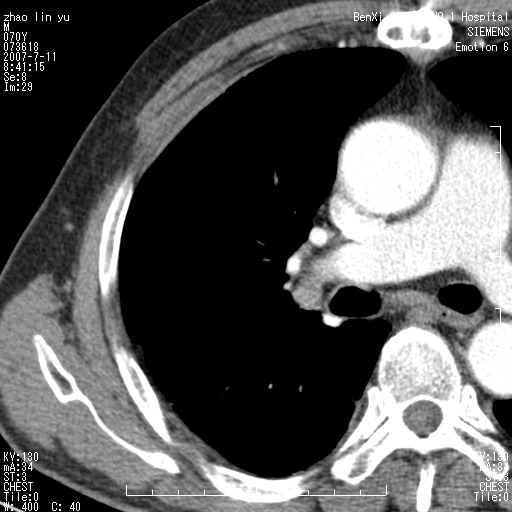

以下是引用王靖旗在2007-7-10 17:12:00的发言:[br] 男、70、咳嗽两个月,半年前换瓣手术,胸片未见异常,于昨天行x片发现右肺上野大片影,行ct扫描,这里是减薄图像,余肺正常。明天晚上会有增强扫描片,到时我会上传。[br][br] 冠状位请大家细看,应该是有意义的,[br][br] 请大家先看平扫发表意见。[br][br]

以下是引用zhangzhongshou在2007-7-10 21:43:00的发言:[br]右肺上叶周围型肺癌,以孤立型细支气管肺泡癌可能性大。